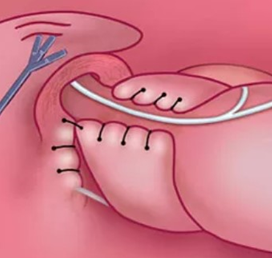

Целью операции при скользящей грыже пищеводного отверстия диафрагмы является восстановление анатомических соотношений в зоне пищевода и желудка. Во время оперативного вмешательства диафрагмальное отверстие ушивается до нормальных размеров (4 см) методом крурорафии. Также хирургическим путем создается антирефлюксный механизм, который способен предотвратить заброс желудочного содержимого в пищевод.

Для сохранения работы клапана и естественных механизмов защиты — рвоты и срыгивания — в большинстве европейских клиник используется парциальная фундопликация по Тоупе на 270 градусов (Toupet 270). В этом случае нижняя часть пищевода и верхняя треть желудка перемещаются до анатомического положения, отверстие в диафрагме ушивается до нормального размера. Из верхней части желудка формируется симметричная манжета, охватывающая пищевод на 270 градусов. Усиливая нижний сфинктер пищевода, манжета будет предотвращать обратный заброс содержимого желудка.

Авторская методика при операции скользящей грыжи пищевода

Для улучшения результатов лечения я усовершенствовал фундопликацию по Тоупе 270, на модифицированную методику получен патент. В основе технологии лежит бережное оперирование, формирование функционального клапана и восстановление естественных соотношений верхней части брюшной полости. Восстанавливается также в послеоперационном периоде физиологическая работа сфинктера пищевода. А это значит, что пациентам, прошедшим оперативное лечение, возвращена возможность вести образ жизни без необходимости приема медикаментов и соблюдения строгой диеты. Согласно статистики, рецидивы спустя год после операции в нашей клинике развиваются не более чем у 2% прооперированных.

Благодаря использованию в ходе операции аппарата электротермического лигирования тканей удается «заваривать» сосуды без излишнего травмирования соседних структур. В ходе создания манжеты, охватывающей пищевод на 270 градусов, остается свободной передне-правая часть, где проходит блуждающий нерв, иннервирующий легкие, сердце и все нижележащие отделы желудочно-кишечного тракта. Использование видеоэндоскопического оборудования позволяет выполнять все манипуляции с предельной точностью, поэтому риск интраоперационных осложнений исключен.

Окончательный вид операционного поля после крурорафии и физиологической фундопликации по Тоупе (270 град)